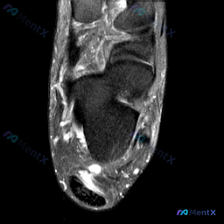

这是一张踝关节MRI冠状位T2加权图像,针对影像的观察结果整理如下:

- 骨性结构:胫骨、腓骨远端及距骨形态基本正常,骨髓信号无明显异常,没有急性骨挫伤、骨髓水肿,也没有明显游离骨块或严重骨质增生

- 韧带结构:内踝下方三角韧带区可见显著高信号,信号模糊增厚,连续性欠佳,是最明显的异常;外侧韧带仅显示部分,无类似严重水肿表现

- 肌腱结构:胫骨后肌腱、趾长屈肌腱、腓骨长短肌腱走行正常,无明显断裂、腱鞘积液或信号异常

- 软组织与关节腔:胫距关节间隙可见明显高信号积液,内踝皮下及深部软组织可见弥漫性高信号,符合软组织水肿表现